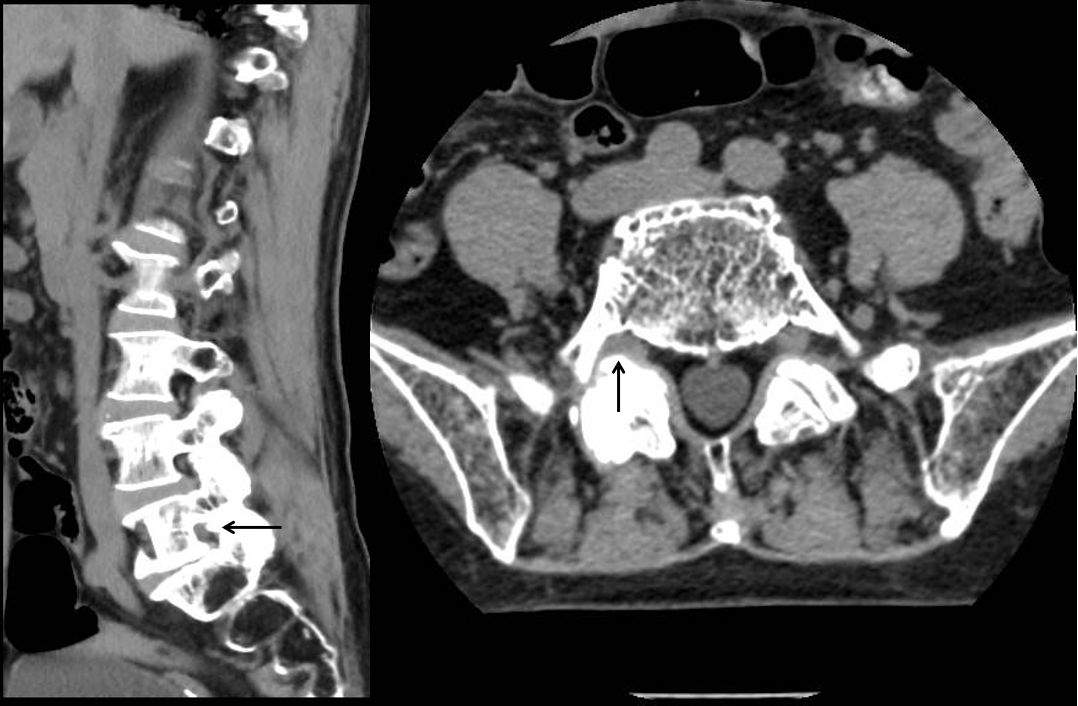

术前CT

接诊后,中山三院脊柱外科派驻中山三院粤东医院的专家刘仲宇主任指导团队为苏女士进行了系统评估。通过详细的病史询问、体格检查并结合影像学资料,刘主任敏锐发现其右下肢疼痛根源并非此前其他医院诊断的“腰椎间盘突出”、“肌肉劳损”或者“神经系统病变”,而很可能是由L5-S1右侧椎间孔狭窄导致的右侧L5神经根受压所引起。“椎间孔是神经根穿行的通道,当这个空间因骨质增生、韧带肥厚等原因变窄时,神经就会被卡住,引发剧烈疼痛。”刘主任解释道。

为了进一步明确诊断,团队为患者实施了选择性右侧L5神经根造影及封闭检查,在透视下将药物精准注射至疑似病变神经根周围,以达到暂时麻痹病变神经根的目的。注射药物前患者在手术室坐2分钟即出现右下肢疼痛难忍的情况,而注射后立即让患者再次尝试坐位7分钟后仍未出现右下肢不适。说明右侧L5神经根就是病变神经根,证实了诊疗团队的病因推测,明确了诊断。